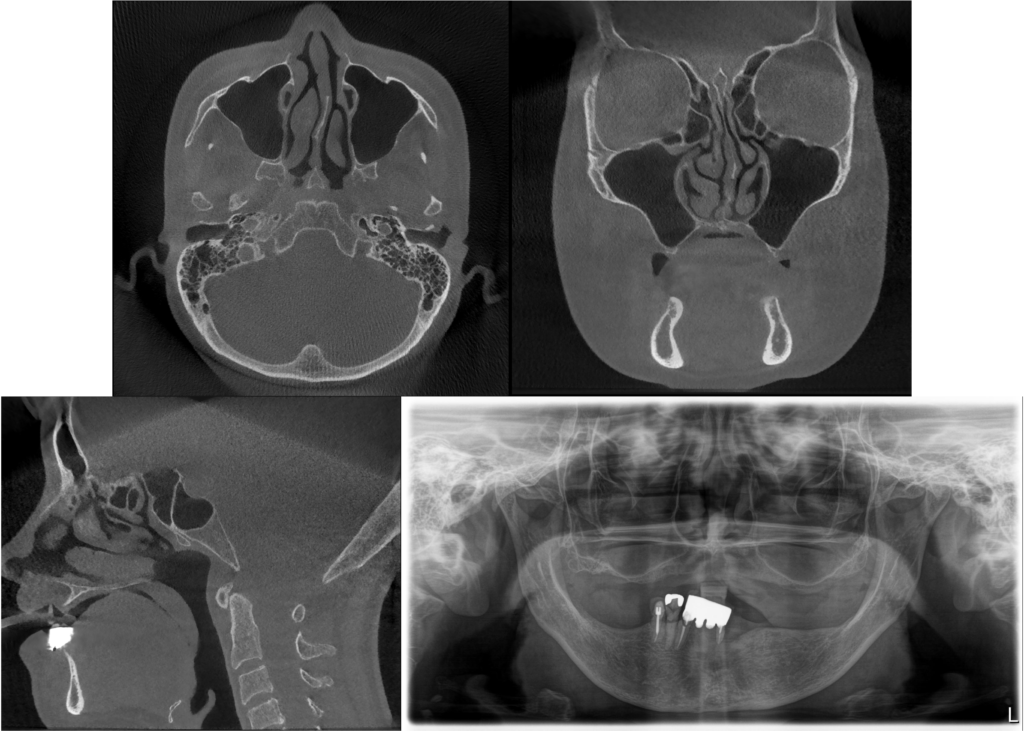

Bedrossianの分類より、ZoneⅠ〜Ⅲいずれにも十分な骨を認めないことから、Insufficient Boneと判断ができ、ノーマルインプラントは困難であることが考えられる。上顎はAll-on-4のためにはザイゴマインプラントが4本必要であることが考えられる。下顎は十分な歯槽骨量があることから、ノーマルインプラント4本を埋入することが可能であると考えられる。また、上顎のザイゴマインプラントの埋入に関しては、 ZAGA分類のType3とType4が混在しているため、ザイゴマインプラントが困難であることが予想される。